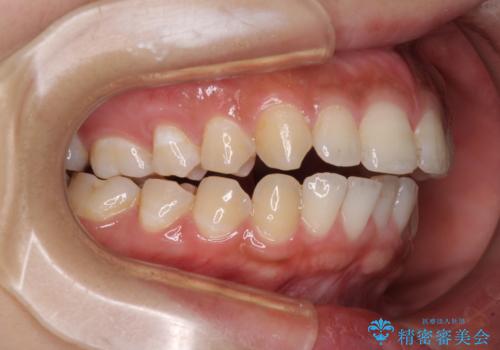

- 口元の突出感と上下前歯のズレを気にして来院された患者様です。

舌の突出癖により上下の前歯は非接触であり、更には奥歯の咬み合わせが非対称となっている状態でした。

舌のトレーニングを行わないと上下前歯の接触達成は困難であるため、トレーニングをしっかりと行っていただきながら、治療を進めて行くこととしました。

通常は上下左右の第一小臼歯4本を抜歯することになりますが、右側臼歯部の咬合が上顎前突気味であったため、下顎右側のみ第二小臼歯を抜歯し、ワイヤー装置にて矯正治療を行うこととしました。

第二小臼歯抜歯はイレギュラーな治療手段であり、治療期間が延びる傾向にありますが、舌のトレーニングをしっかりと行ってくださり、2年弱という非常に短い期間で理想的な仕上がりを達成することができました。